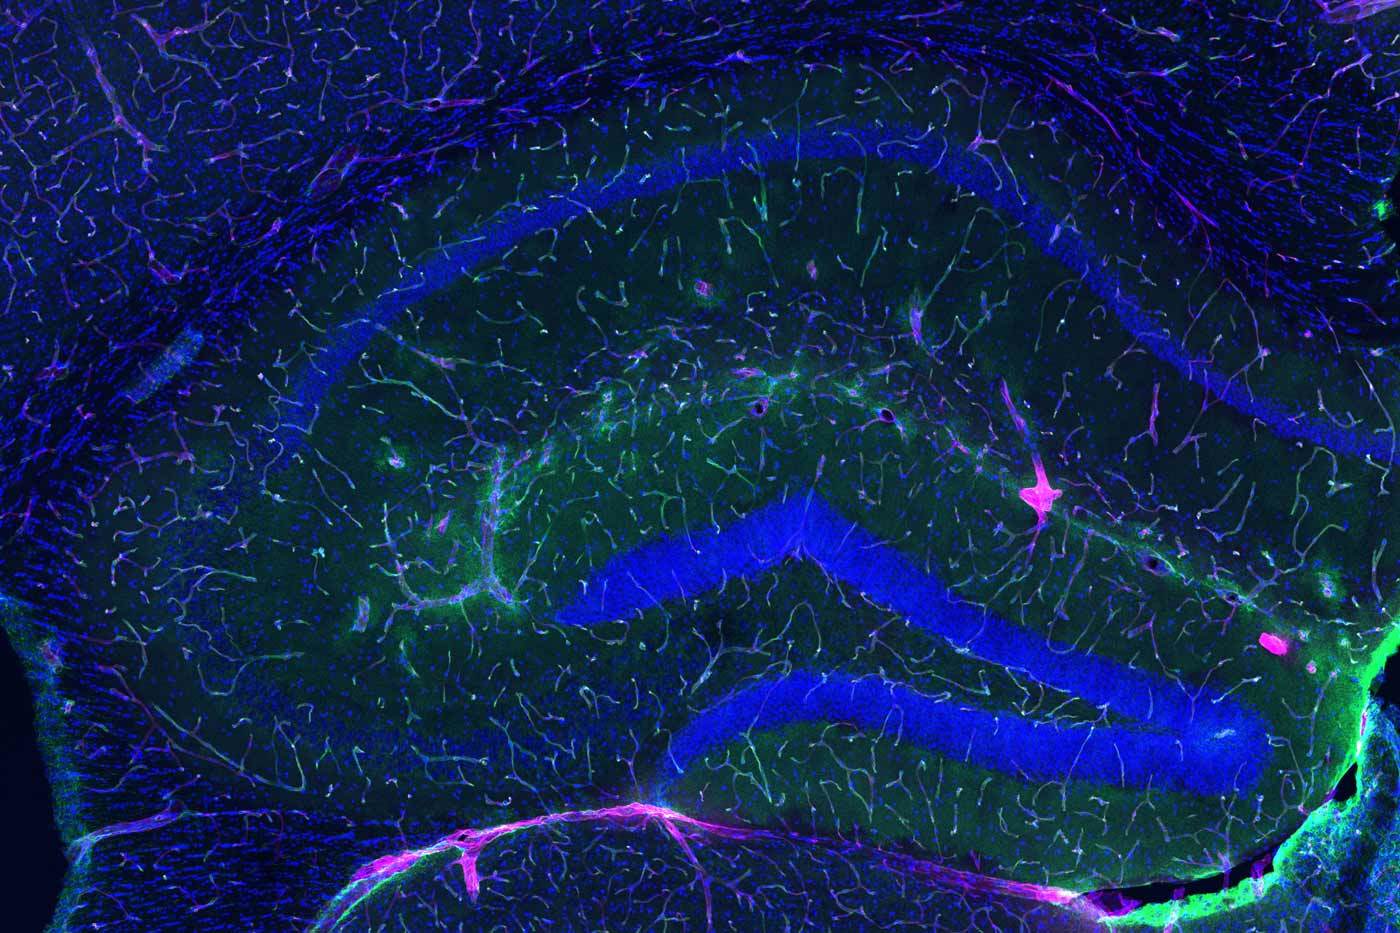

젊은 생쥐의 혈액-뇌 장벽(녹색선)은 주입된 연료(이물질) 대부분이 뇌에 도달하는 것을 막는다. 사울 빌레다 박사 연구실 제공.

반대로 운동을 하면 간에서 생성된 GPLD1이 혈류를 타고 뇌를 둘러싼 혈관으로 이동해 세포 표면에서 NAP을 잘라내 제거한다. 이로 인해 혈액-뇌 장벽의 구조적 완전성이 회복되고 염증이 감소하는 것으로 나타났다.

연구진은 GPLD1이 뇌에서 어떻게 작용하는지 이해하기 위해 이 효소의 기본 기능에 주목했다. GPLD1은 세포 표면의 특정 단백질을 절단하는 역할을 한다. 연구진은 효소에 의해 잘릴 가능성이 있는 단백질이 존재하는 조직을 찾았고, 노화와 함께 이러한 단백질이 더 많이 쌓일 것으로 추정했다.

혈액-뇌 장벽을 구성하는 세포는 GPLD1의 표적이 될 수 있는 여러 단백질을 갖고 있었다. 그러나 실험실에서 각각을 시험한 결과, 실제로 GPLD1이 제거한 것은 TNAP 하나뿐이었다.